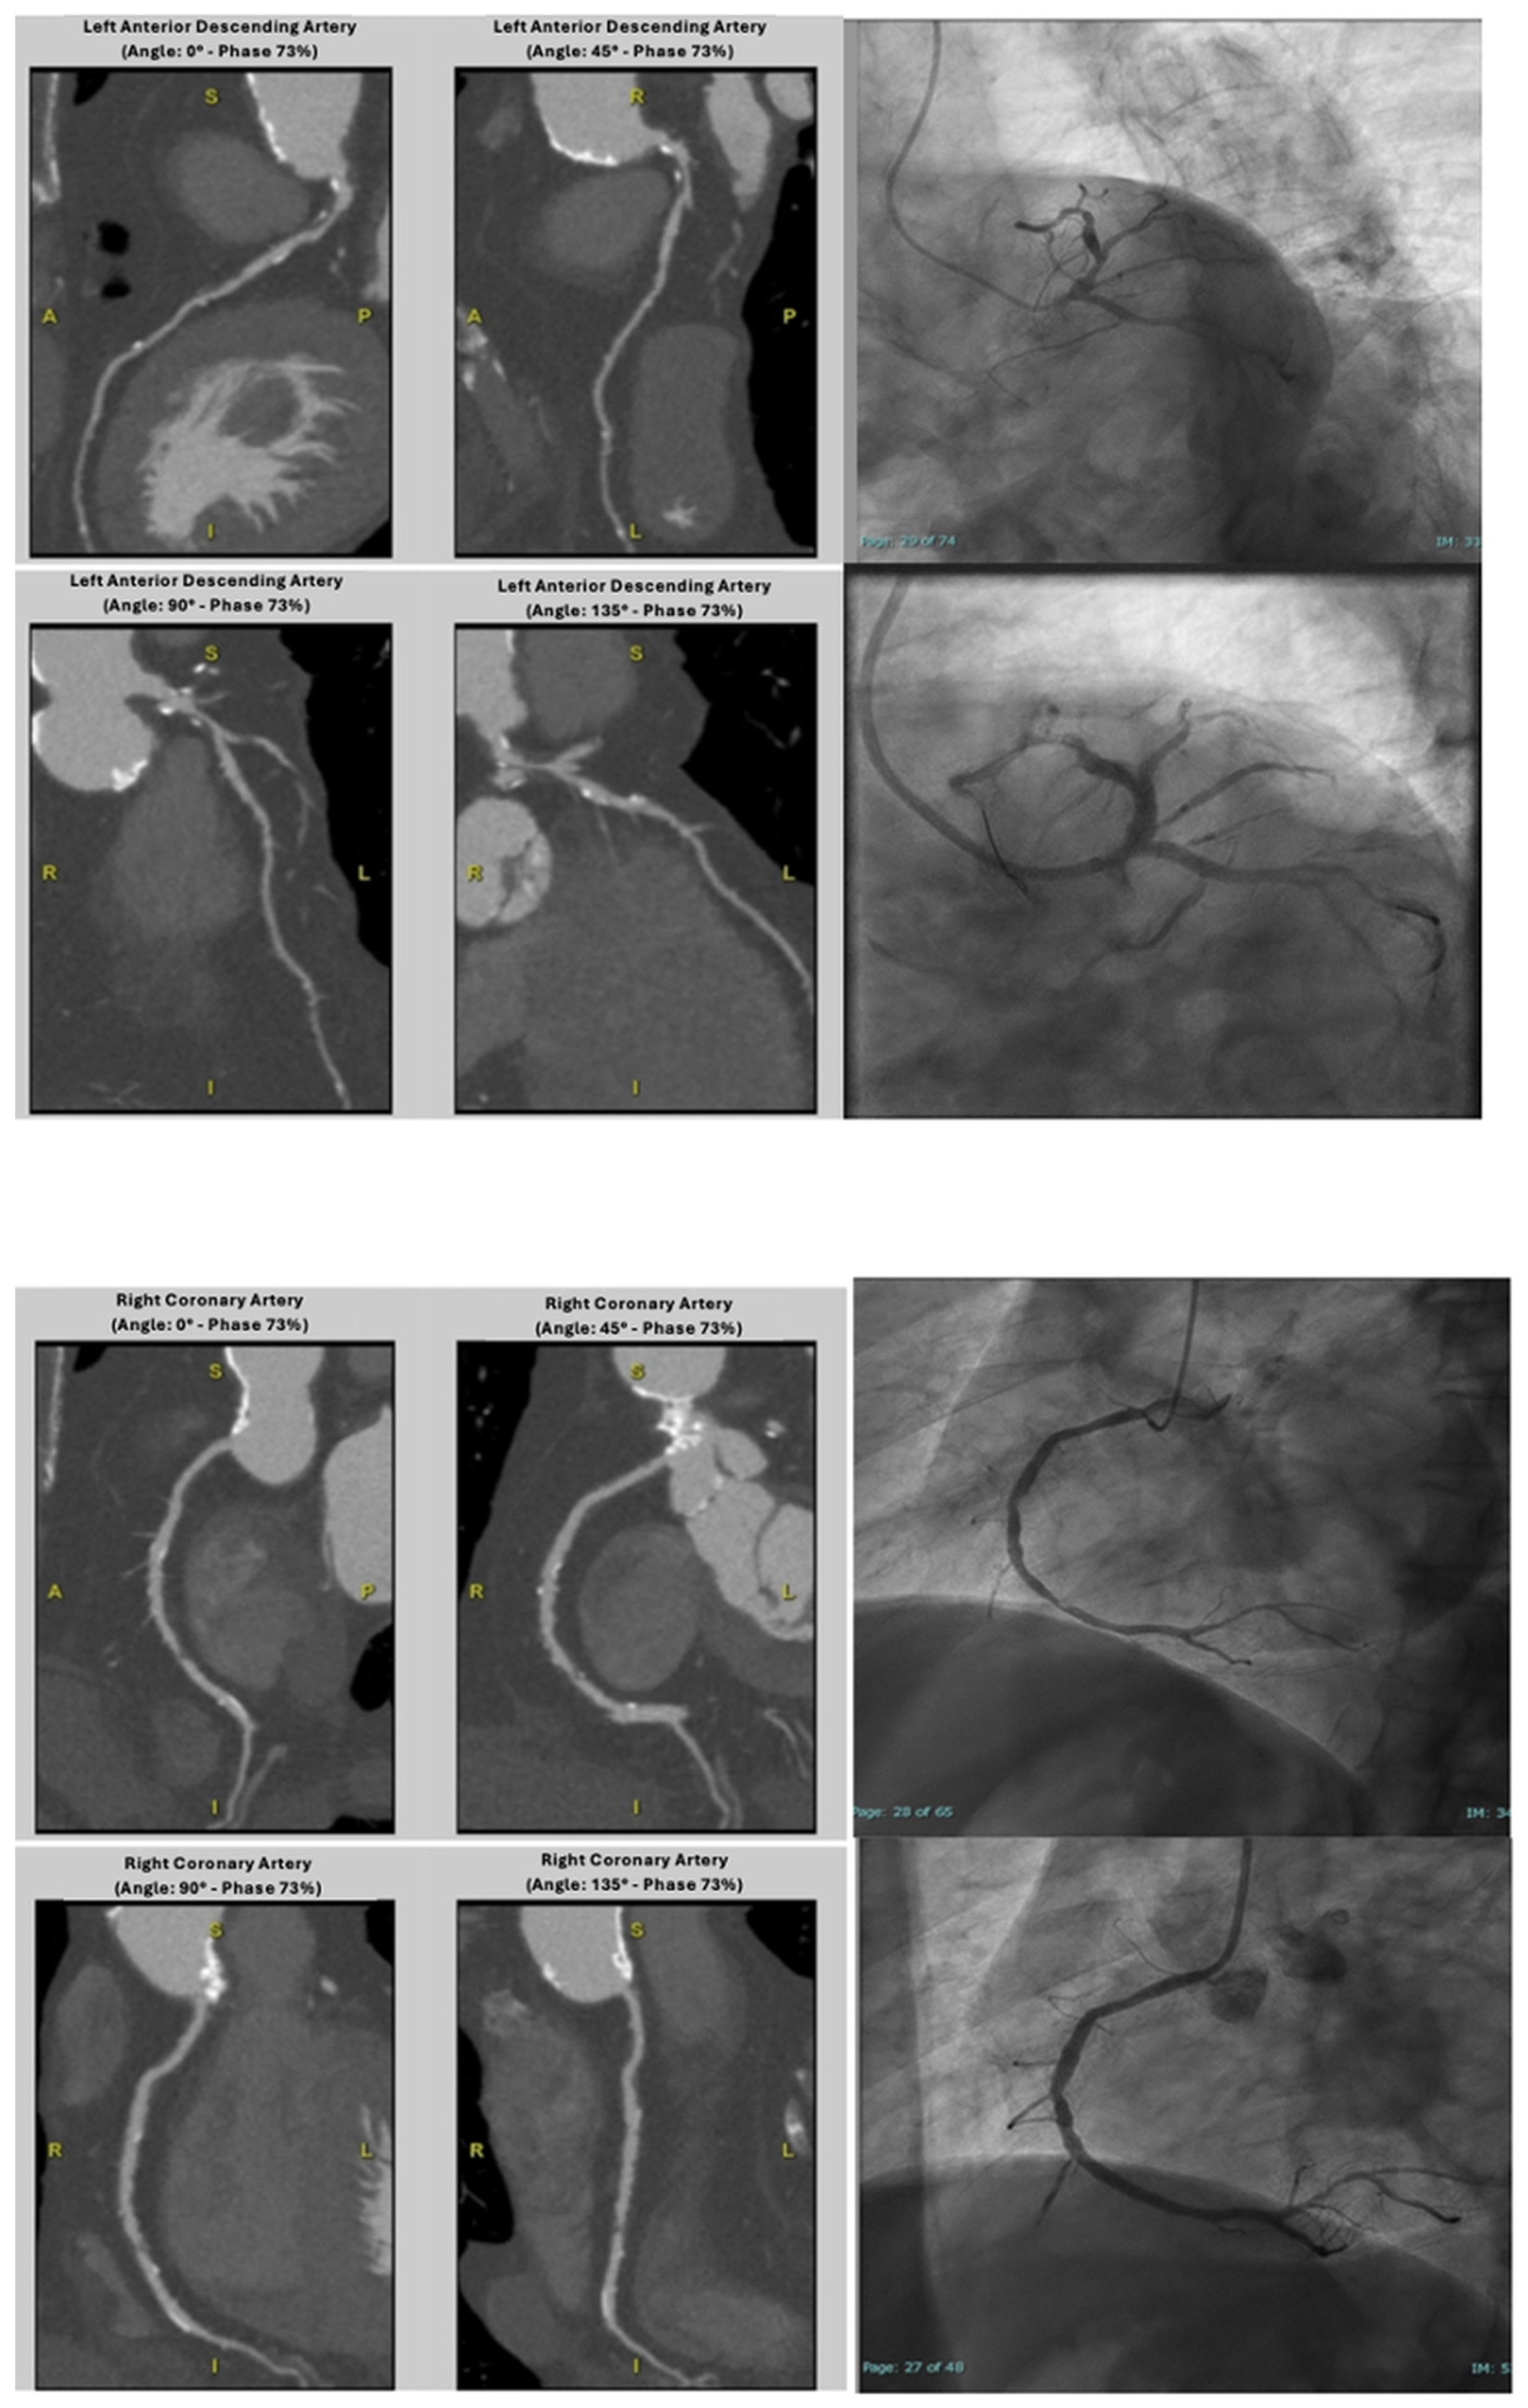

4.1. Coronary CTA Findings in Patients-Based Analysis

4.2. Coronary CTA Findings in Vessel-Based Analysis